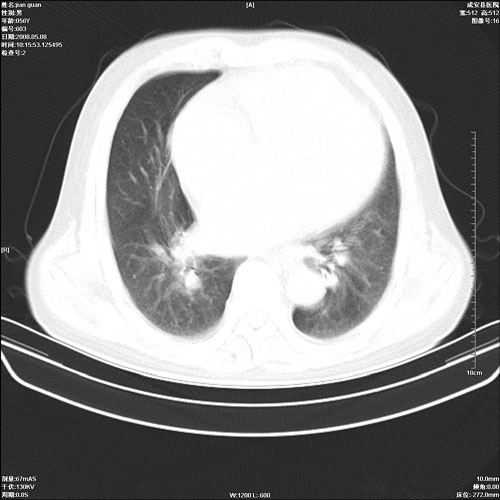

病人 男 60岁 主诉 胸闷 无明显发热 一般情况尚可。

肺结核?

两上肺陈旧性结核;慢支肺气肿、伴感染?

考虑1心功不全,肺水肿

2右上肺结核纤维性病灶、肺气肿

1.右上肺陈旧性肺结核.

2.心脏增大(以左心室增大为著),请结合b超及听诊.

1.两上肺陈旧性结核;慢支肺气肿。

2.肺门血管扩张,心脏增大,为肺心病

考虑.两上肺陈旧性结核;慢支肺气肿。肺心病

两上肺陈旧性结核,慢支肺气肿。

两上肺陈旧性结核;慢支肺气肿。肺肺间质纤维化

1.陈旧肺结核;

2.慢支肺气肿;

3.肺心病.

陈旧性肺结核,左心房扩大,左心衰竭